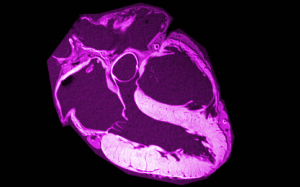

ΜΑΓΝΗΤΙΚΗ ΚΑΡΔΙΑΣ

Η μαγνητική τομογραφία καρδιάς αποτελεί μία από τις ταχέως εξελισσόμενες απεικονιστικές τεχνικές με ευρύτατες πλέον ενδείξεις και σημαντική συνεισφορά στη βαθύτερη κατανόηση και αποτελεσματική αντιμετώπιση των καρδιολογικών παθήσεων.